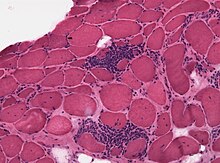

A neuromuscular disease is any disease affecting the peripheral nervous system (PNS),[lower-alpha 1] the neuromuscular junction, or skeletal muscle, all of which are components of the motor unit.[4] Damage to any of these structures can cause muscle atrophy and weakness. Issues with sensation can also occur.

Neuromuscular diseases can be acquired or genetic. Mutations of more than 500 genes have shown to be causes of neuromuscular diseases.[5] Other causes include nerve or muscle degeneration, autoimmunity, toxins, medications, malnutrition, metabolic derangements, hormone imbalances, infection, nerve compression/entrapment, comprised blood supply, and trauma.[6]

Symptoms of neuromuscular disease may include numbness, paresthesia, muscle weakness, muscle atrophy, myalgia (muscle pain), and fasciculations (muscle twitches).[2][7]

Neuromuscular disease can be caused by autoimmune disorders,[1] genetic/hereditary disorders[2] and some forms of the collagen disorder Ehlers–Danlos syndrome,[8] exposure to environmental chemicals and poisoning which includes heavy metal poisoning.[3] The failure of the electrical insulation surrounding nerves, the myelin, is seen in certain deficiency diseases, such as the failure of the body's system for absorbing vitamin B-12.[3]

Diseases of the motor end plate include myasthenia gravis, a form of muscle weakness due to antibodies against acetylcholine receptor,[9][10] and its related condition Lambert–Eaton myasthenic syndrome (LEMS).[11] Tetanus and botulism are bacterial infections in which bacterial toxins cause increased or decreased muscle tone, respectively.[12] Muscular dystrophies, including Duchenne's and Becker's, are a large group of diseases, many of them hereditary or resulting from genetic mutations, where the muscle integrity is disrupted, they lead to progressive loss of strength and decreased life span.[13]